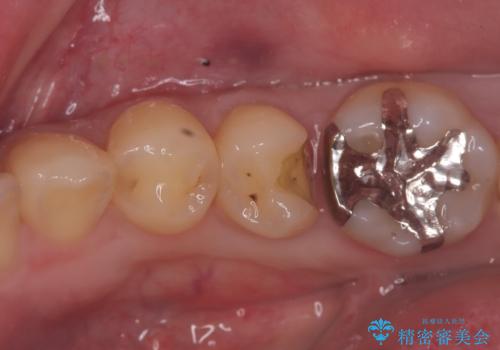

銀歯を外し、インプラントを入れたい